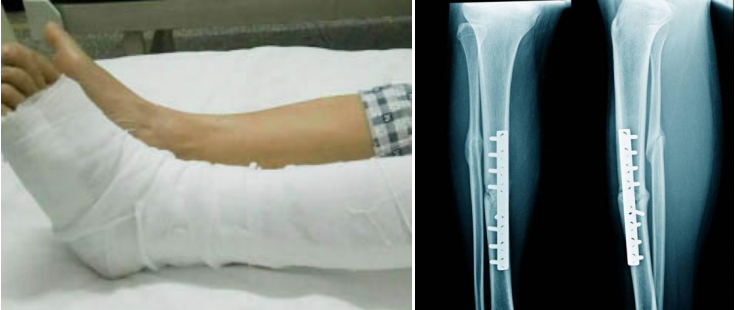

1.各種骨傷、內(nèi)固定術(shù)后;

運(yùn)用傳統(tǒng)康復(fù)技術(shù)如中藥熏蒸、針灸、推拿等與現(xiàn)代物理治療技術(shù)動(dòng)態(tài)關(guān)節(jié)松動(dòng)術(shù)、麥特蘭德手法、肌內(nèi)效貼、筋膜刀治療、蠟療、理療相結(jié)合,針對(duì)各關(guān)節(jié)骨傷、手外傷、運(yùn)動(dòng)損傷、截肢后康復(fù)、人工關(guān)節(jié)置換術(shù)后進(jìn)行康復(fù)訓(xùn)練和治療。